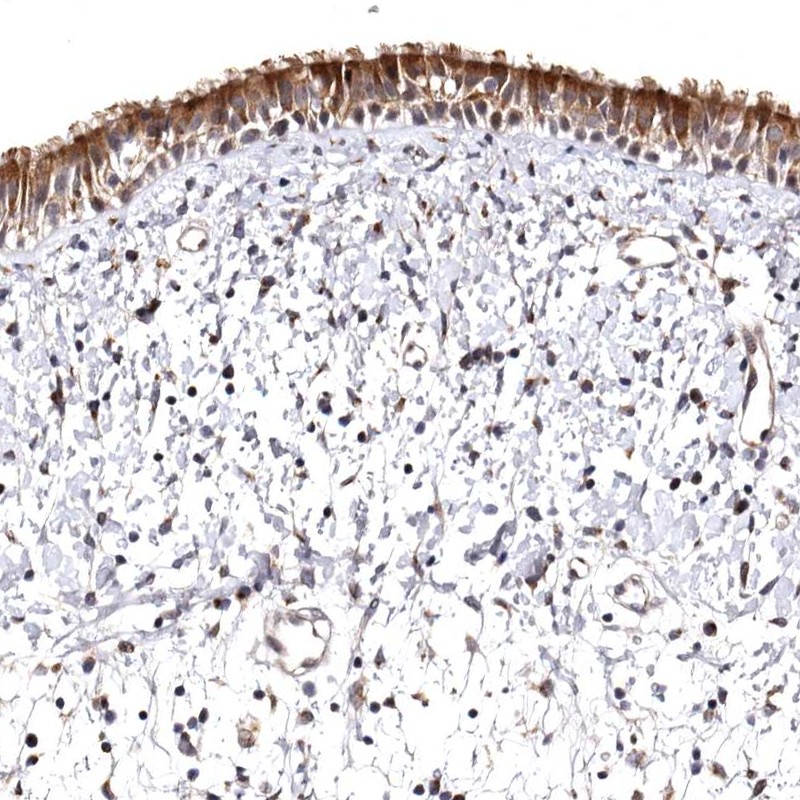

Immunohistochemical staining of human nasopharynx shows strong cytoplasmic positivity in respiratory epithelial cells.